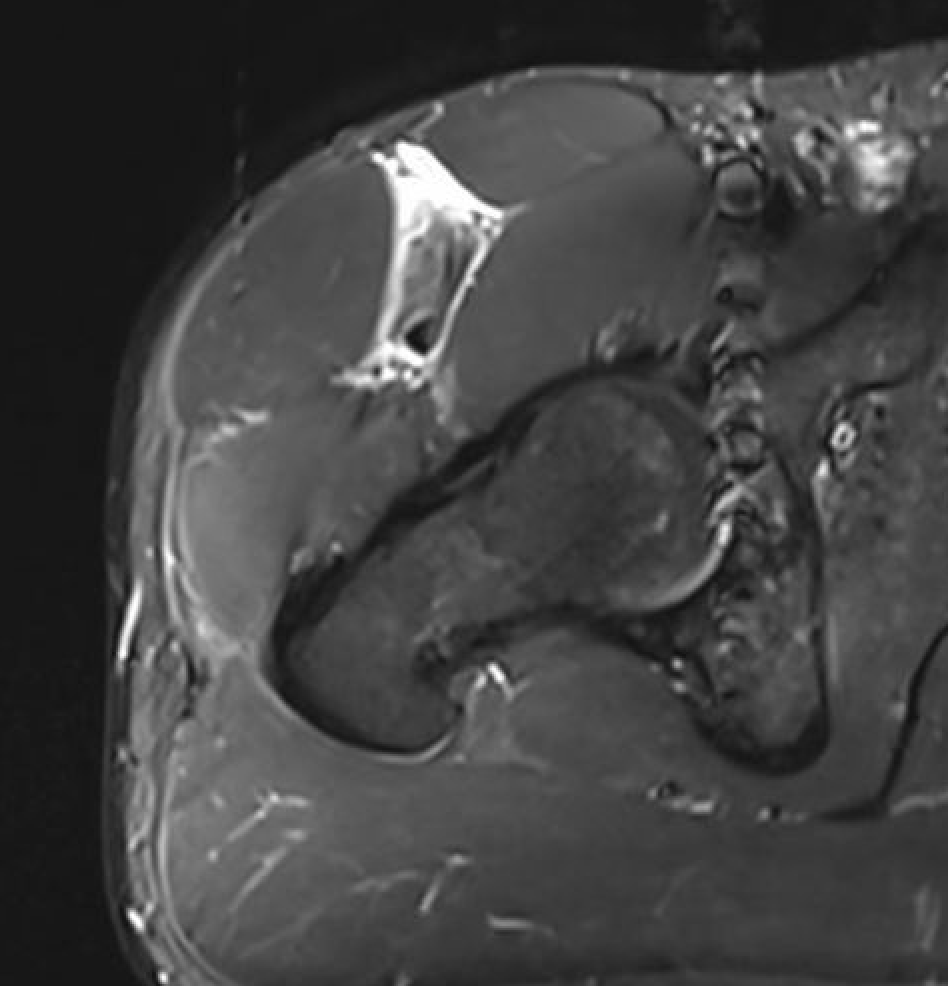

Quadriceps muscle tears

British Athletics Muscle Injury Classification (MRI)